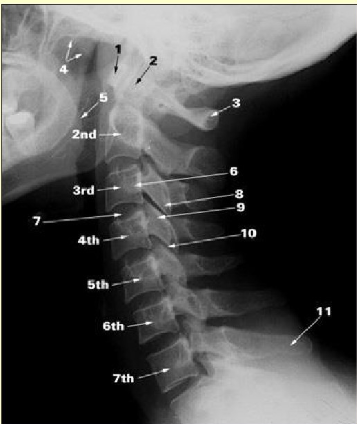

Label this image

anterior arch of the atlas

dens of axis

posterior arch of atlas

soft palate

root of tongue

transverse process

intervertebral disc

inferior articular process

superior articular process

facet joint

spinous process of C7